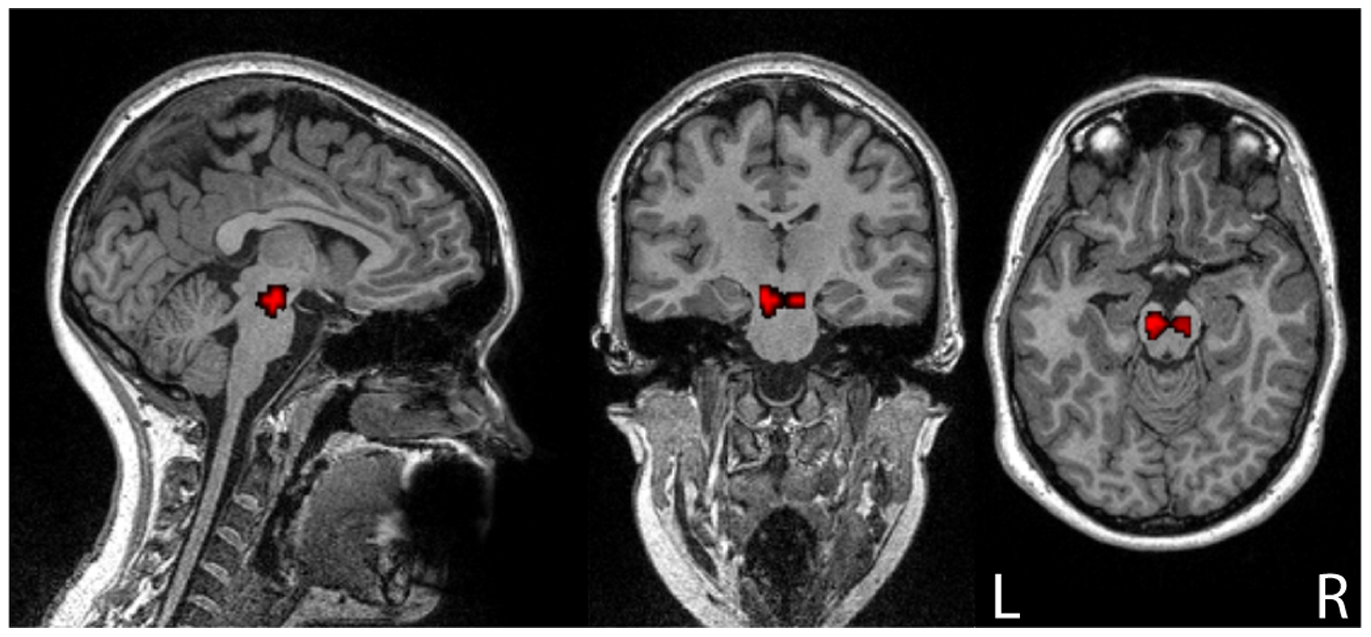

This week, scientists from the University of Texas at Austin contributed a novel idea to addiction research. Focusing on glutamatergic synaptic transmission, the primary mode of excitatory signaling in the central nervous system, the group hypothesized that social stress would lead to increased vulnerability to cocaine addiction. Specifically, the ventral tegmental area (VTA) of the brain, a prime location for dopamine reward activity, was tested in rats that had experienced social stress.

The results of the experiments indicate that enhancement of neurotransmission, known as synaptic plasticity, is more likely to occur in the VTA following stress exposure. This finding is particularly important in the context of cocaine addiction, as the reward system for this process is located in the same area.